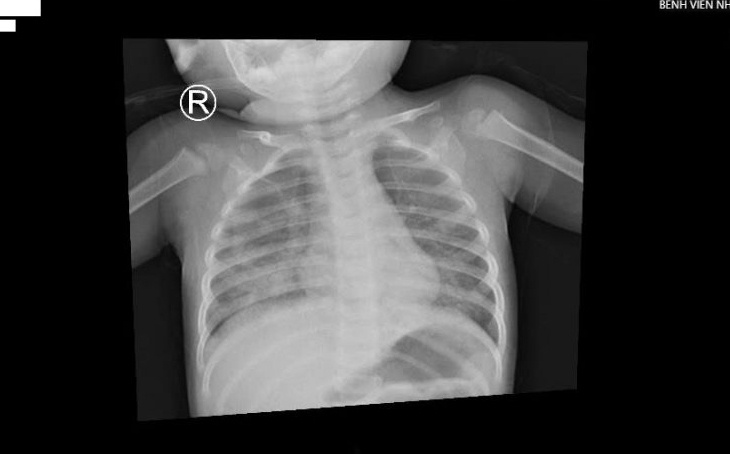

Nhập viện trong tình trạng khó thở, tím tái, bệnh nhi được chẩn đoán viêm phổi, tổn thương lan toả 2 phế trường gây suy hô hấp nặng.